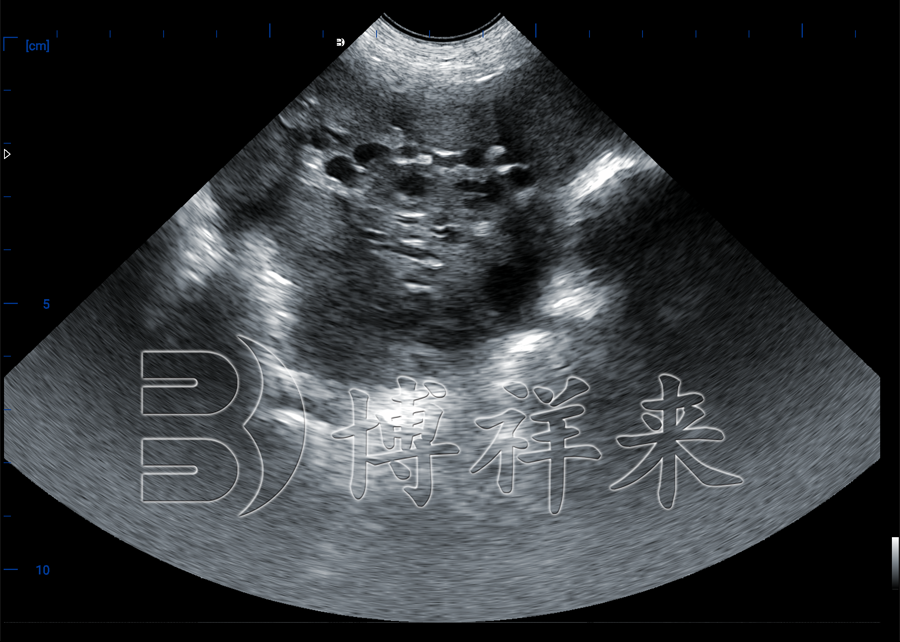

在卵巢检查中,卵泡通常表现为 圆形或椭圆形的液性暗区,边界清晰,内部为低回声或无回声。随着发情周期的推进,卵泡逐渐长大,直径在排卵前可达到 6~8毫米。通过B超图像,技术人员不仅能判断卵泡是否成熟,还能推测母猪排卵的时间。

借助猪用B超机,养殖户可以直观判断母猪卵泡的发育程度,从而确定***配种时间。